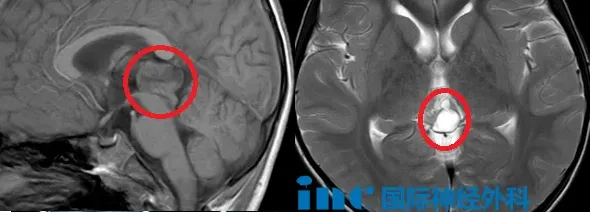

鑫鑫的故事从一次意外开始。2021年,他在摔伤后做了头部CT扫描,医生在影像上发现了一个不该出现的东西:大脑深处有个异常阴影,还伴着钙化。后续的MRI进一步确认——松果体区长了一个肿瘤,大小约22×14×17毫米。

确诊后,鑫鑫定期拍片随访。在2023年7月的MRI上,肿瘤已经长到了25×19×15毫米。与此同时,他的症状加重了——睡眠更乱、注意力涣散、记忆力下滑、甚至出现了心理行为的异常。医生们开始有了分歧:到底该不该手术?有人说观察,有人说必须切。但鑫鑫的持续恶化已经给出了答案——这个肿瘤不是静止的,它在吞噬这个孩子的大脑。

这个案例背后的医学原理是什么?第一,松果体肿瘤的首选诊断工具是MRI。通过精细的核磁共振扫描,医生可以准确看到肿瘤的位置、大小和与周围组织的关系,甚至能和良性的松果体囊肿鉴别开来。第二,当肿瘤出现症状、在影像上有进展迹象、或者无法完全排除恶性可能时,应该积极考虑手术。不是所有松果体肿瘤都要动刀,但一旦决定动,就要做到全切。第三,松果体细胞瘤全切后的预后极好——5年生存率90%以上。第四,在拥有先进显微技术和神经电生理监测设备的神经外科中心,这类手术可以在实现肿瘤完全切除的同时,最大程度保护周围的神经功能。